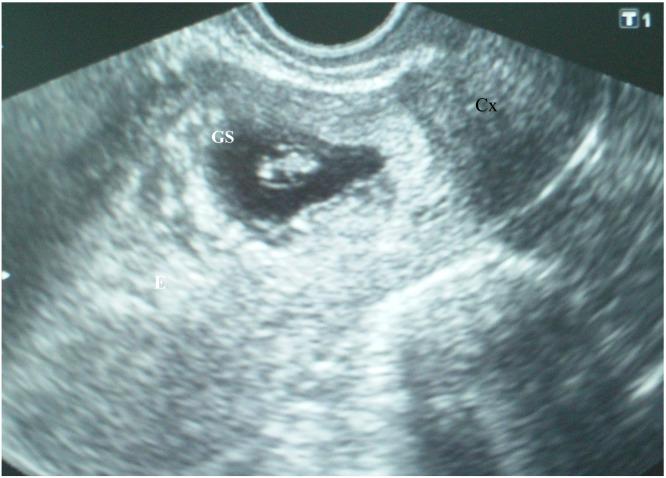

Cesarean scar pregnancy (CSP) is a rare form of ectopic pregnancy, defined as the implantation of the gestational sac at the uterine incision scar of the previous cesarean section. This condition is associated with severe maternal and fetal/neonatal complications, including severe bleeding, rupture of the uterus, fetal demise, or preterm delivery. In view of these, early diagnosis allows the option of termination of pregnancy. In this case report, we present a patient with a cesarean scar pregnancy who was diagnosed at the sixth week of gestation but declined early termination of the pregnancy and was managed to the 38th week. Placenta previa was confirmed in the second trimester. A planned cesarean section was performed that resulted in the birth of a live full-term neonate. Intraoperatively, placenta percreta was diagnosed, and due to uncontrollable bleeding, a hysterectomy was performed. The postoperative course was uneventful. In cases where an early diagnosis of CSP is made, women should be counseled that this will almost certainly evolve to placenta previa, and the associated risks should be explained. Close follow-up of CSP is mandatory if expectant management is selected. Further studies are needed for definitive conclusions and to determine the risks of expectant management.

摘要

剖宫产瘢痕妊娠(CSP)是一种罕见的异位妊娠形式,定义为妊娠囊着床于既往剖宫产子宫切口瘢痕处。这种情况与严重的母婴及胎儿/新生儿并发症相关,包括严重出血、子宫破裂、胎儿死亡或早产。鉴于此,早期诊断可选择终止妊娠。在本病例报告中,我们介绍了一名剖宫产瘢痕妊娠患者,其在妊娠第6周被诊断出,但拒绝早期终止妊娠,并一直维持到第38周。孕中期确诊为前置胎盘。计划行剖宫产,结果娩出一名足月活产新生儿。术中诊断为穿透性胎盘植入,因出血无法控制,行子宫切除术。术后过程顺利。在早期诊断出CSP的病例中,应告知女性这种情况几乎肯定会发展为前置胎盘,并解释相关风险。如果选择期待治疗,对CSP进行密切随访是必要的。需要进一步研究以得出明确结论并确定期待治疗的风险。